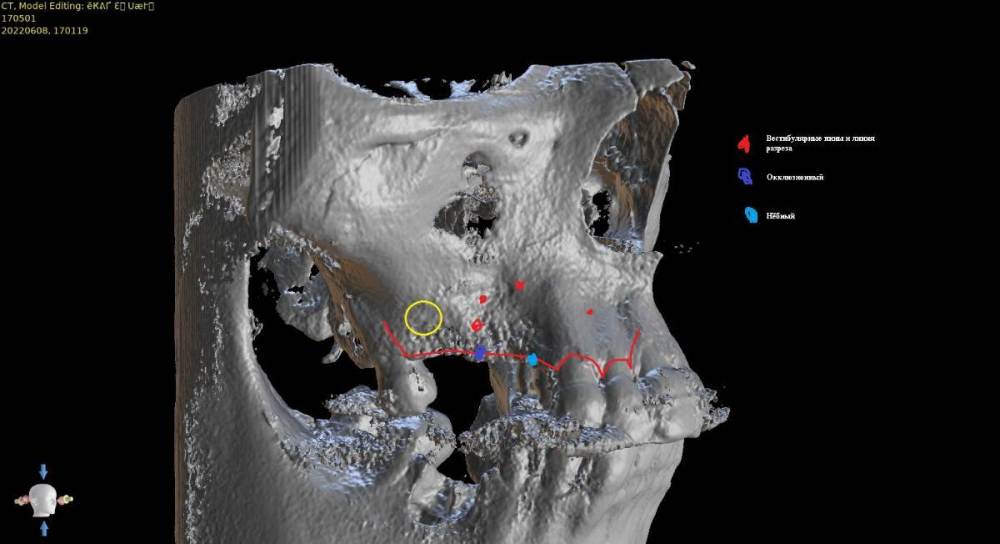

Женька Опубликовано 15 июля, 2022 Поделиться Опубликовано 15 июля, 2022 Коллеги, здравствуйте. Планирую небольшую НКР совместно с ОСЛ в боковом отделе верхней челюсти справа. Вот скрины. На реформате 3д план. Пожалуйста, поделитесь правильно ли мной выбран дизайн лоскута и фиксация мембраны (мембрана будет Creos, кость ауто+ксено (возможно ещё немного алло) p.s вариант обойтись без пластики не предлагать.)) Правильной ортопедической позиции добиться без нкр не выходит, кмк. Да и надо же пробовать как-то. Ссылка на комментарий

stommm Опубликовано 16 июля, 2022 Поделиться Опубликовано 16 июля, 2022 Если уж делать так, то я бы продлил разрез дальше, за 7. Удобнее мобилизовать, ну и медиальный сдвиг лоскута можно сделать. Мембрана 20х30. Дистальный пин на уровне 17, медиальный между 13 и 12. В области синуса пиниться стоит аккуратнее, можно провалиться, по этой же причине не стоит увлекаться работой со скребком в предполагаемой зоне фиксации мембраны. П.с. Померьте расстоянием между коронками. По наклону 17 есть ощущение что места маловато. Иногда в таких случаях проще поставить вертикально 16 ,15 с консолью 14, а не дистально наклонять апексы 16 и 14 1 Ссылка на комментарий

Irouil Опубликовано 18 июля, 2022 Поделиться Опубликовано 18 июля, 2022 Делайте НКР, конечно, если в таком варианте Вы более уверены Вместо пинов всегда можно рассмотреть надкостничные швы - тогда скрестись можно будет более храбро Ссылка на комментарий

major Опубликовано 19 июля, 2022 Поделиться Опубликовано 19 июля, 2022 @Женька Доброго времени суток. Если вы пробуете, то может быть разделить ОСЛ с последующей постановкой имплантов с НКР(сосидж)? Если остаётесь при своём, то согласен с @stommm по дизайну разреза, расположения имплантов и опасений по поводу пинов(если есть тонкое сверло, тоньше ножки пина, то можете предварительно просверлить). Если не уверены что сможете набить сосиску с уверенной постановкой пинов, то лучше сетку или каркасную мембрану(имхо). P.S. - когда делаете КЛКТ просите пациентов надувать щеки, губы или подкладывайте ватные валики. Будет немного удобнее заниматься постановкой. 1 Ссылка на комментарий